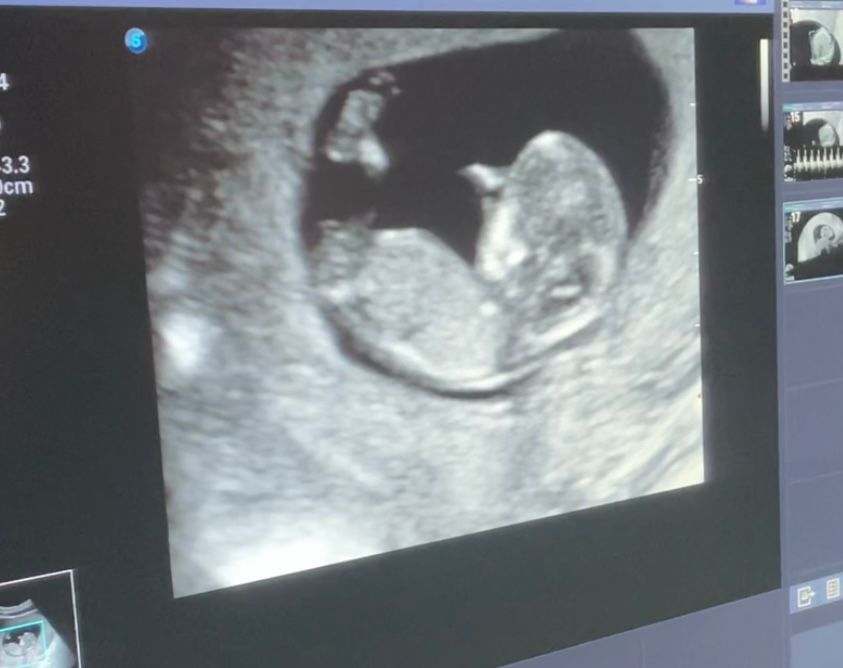

Первый скрининг пройден. 11+6.

Ох уж это томительное ожидание, и волновалась, и предвкушала встречу на экране с малышом) По узи всё в норме, запишу для будущего сравнения некоторые показатели:

КТР 54

БПР 15

ТВП 1.3

ЧСС 154

Прикрепление по передней стенке, носовая кость визуализируется, длина шейки матки 32 мм.

Малыш лежал спокойно, закинув ногу на ногу 😅 Хорошо дал всё посмотреть, умничка, в общем) На 75% предположили пол - девочка 🌸 В 16 недель будет уже точно ясно. Впечатления исключительно положительные, осталось дождаться результатов анализа крови 🤞🏼